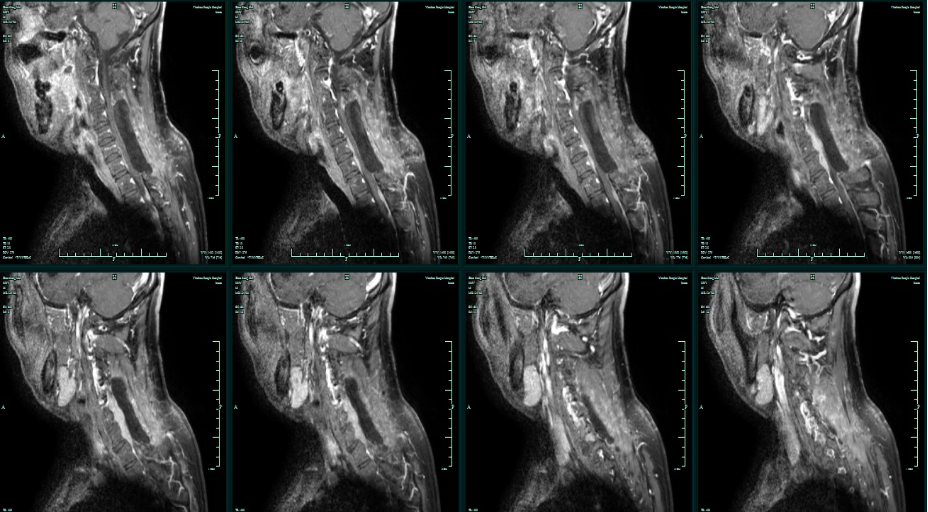

MRI增强:C4-T1椎管内髓外占位,淋巴瘤可能性大。

术前T1平扫

术前T2平扫

术前T1增强

T1增强轴位